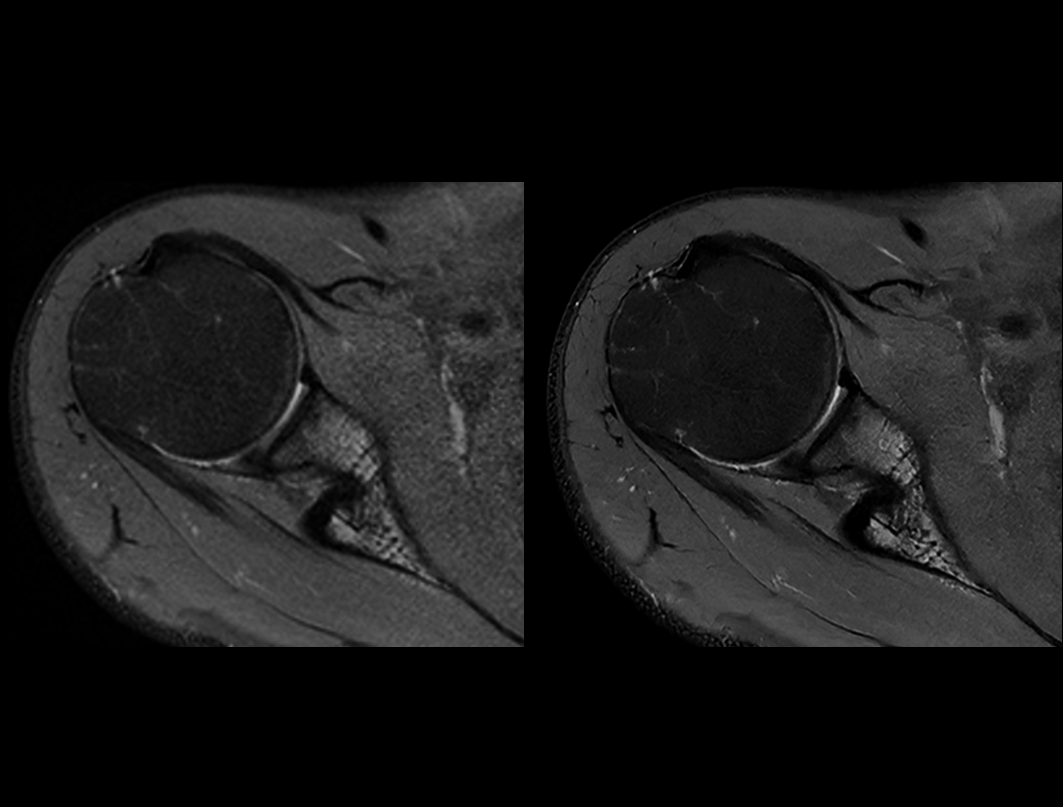

肩关节 PDW FS

常规成像 (2:56 min) vs. uAIFI DeepRecon™ (2:56 min)

0.29×0.29×3 mm3